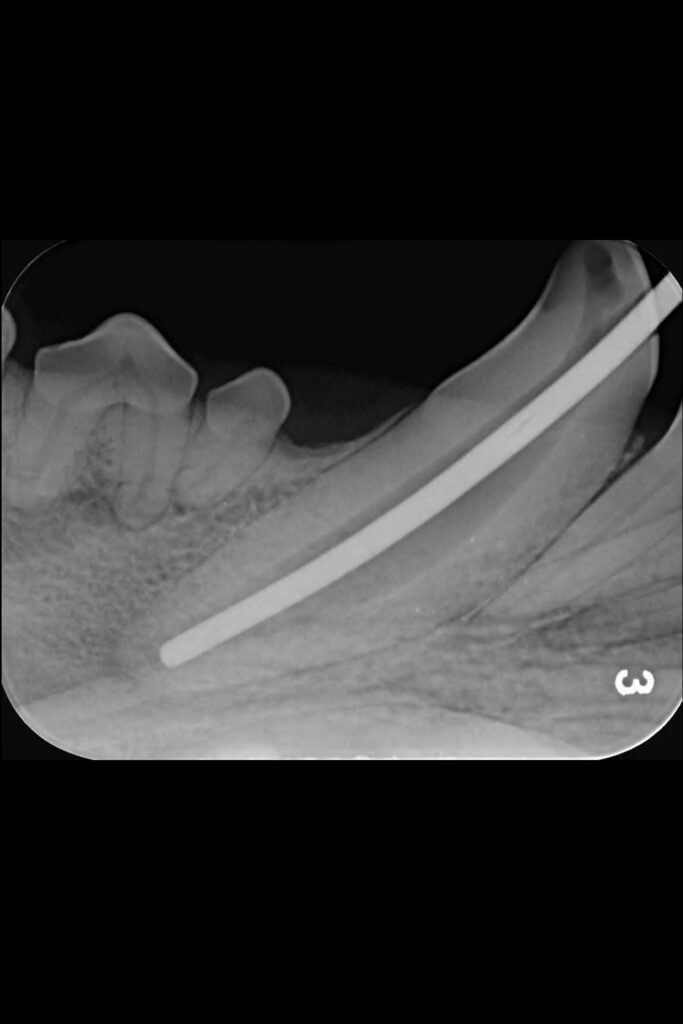

Max’s dental radiographs for his fractured mandibular canine tooth

Radiography Assistant Ellie brought her lovely Labrador Max in to see dentist Hannah after he fractured his lower canine tooth.

Initial radiographs were taken on our intraoral dental-specific X-ray unit to evaluate the dense tooth and bone structure. This revealed what was happening within the tooth and beneath the gumline – all the areas that cannot be seen with a visual examination. These showed not only the crown fracture but also a wide pulp chamber, which required root canal treatment.

A key part of this treatment involves inserting increasing file sizes into the tooth to reach the pulp to remove any infected or necrosed tissue. X-ray images are then again taken at various points throughout the procedure to check file size and position.